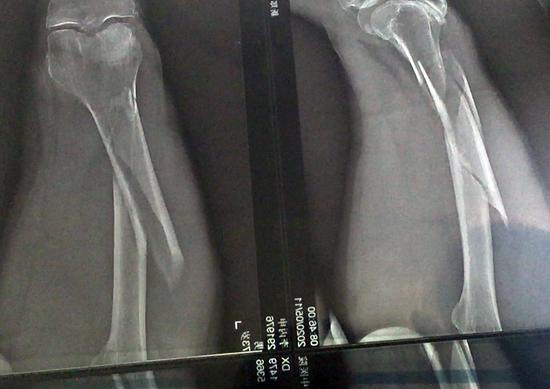

李丙申說,5月11日那天風很大,他們沒接到停工通知,和工友正常施工作業。突然一陣大風把他身邊的在建墻體吹倒了四五米,他躲閃不急被砸傷,后被送至新鄭市中醫院住院治療至今。住院后經醫生診斷李丙申大腿粉粹性骨折,胸部肩部均有骨折。